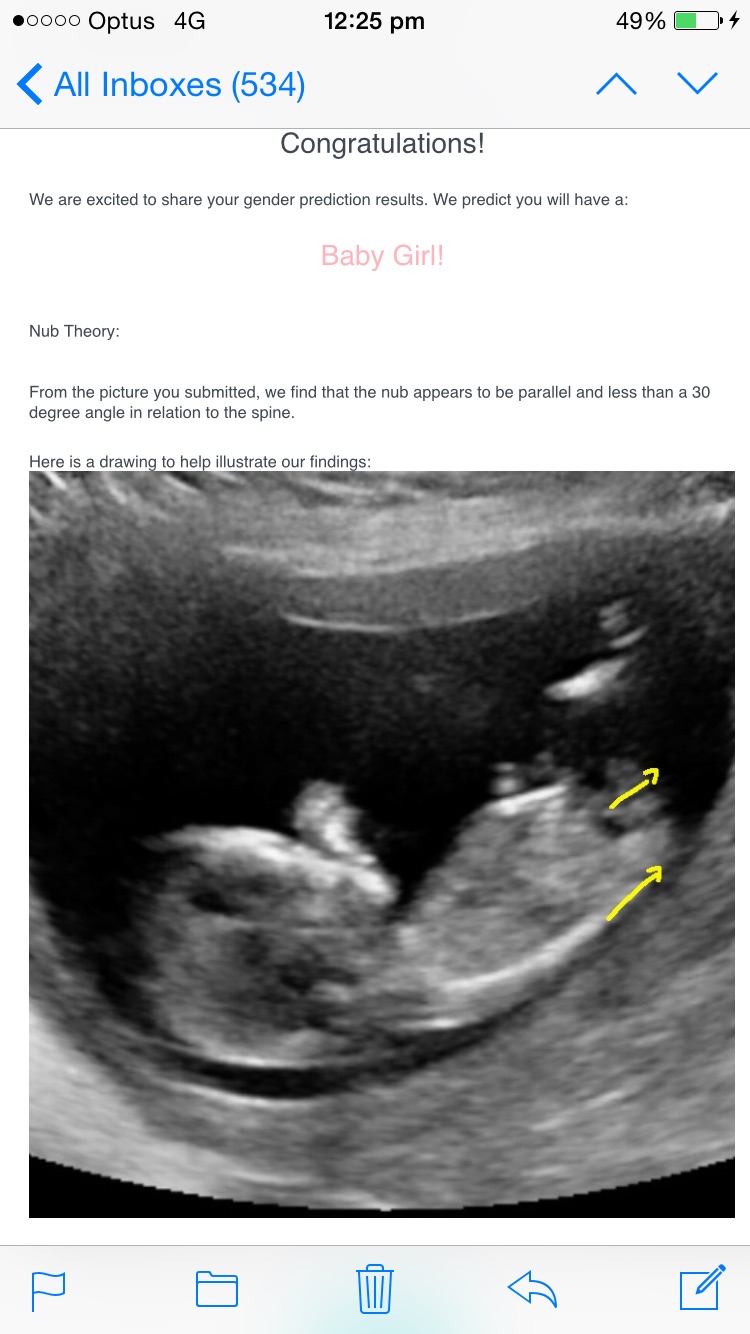

Thanks for the replies :) it's exciting that everyone has guessed boy as I am kind of hoping for a boy. Weird thing, I submitted my pic to the Gender Experts website and they are saying the baby looks like a girl. Any one have any experience with them and could they be wrong? Attachment 34212